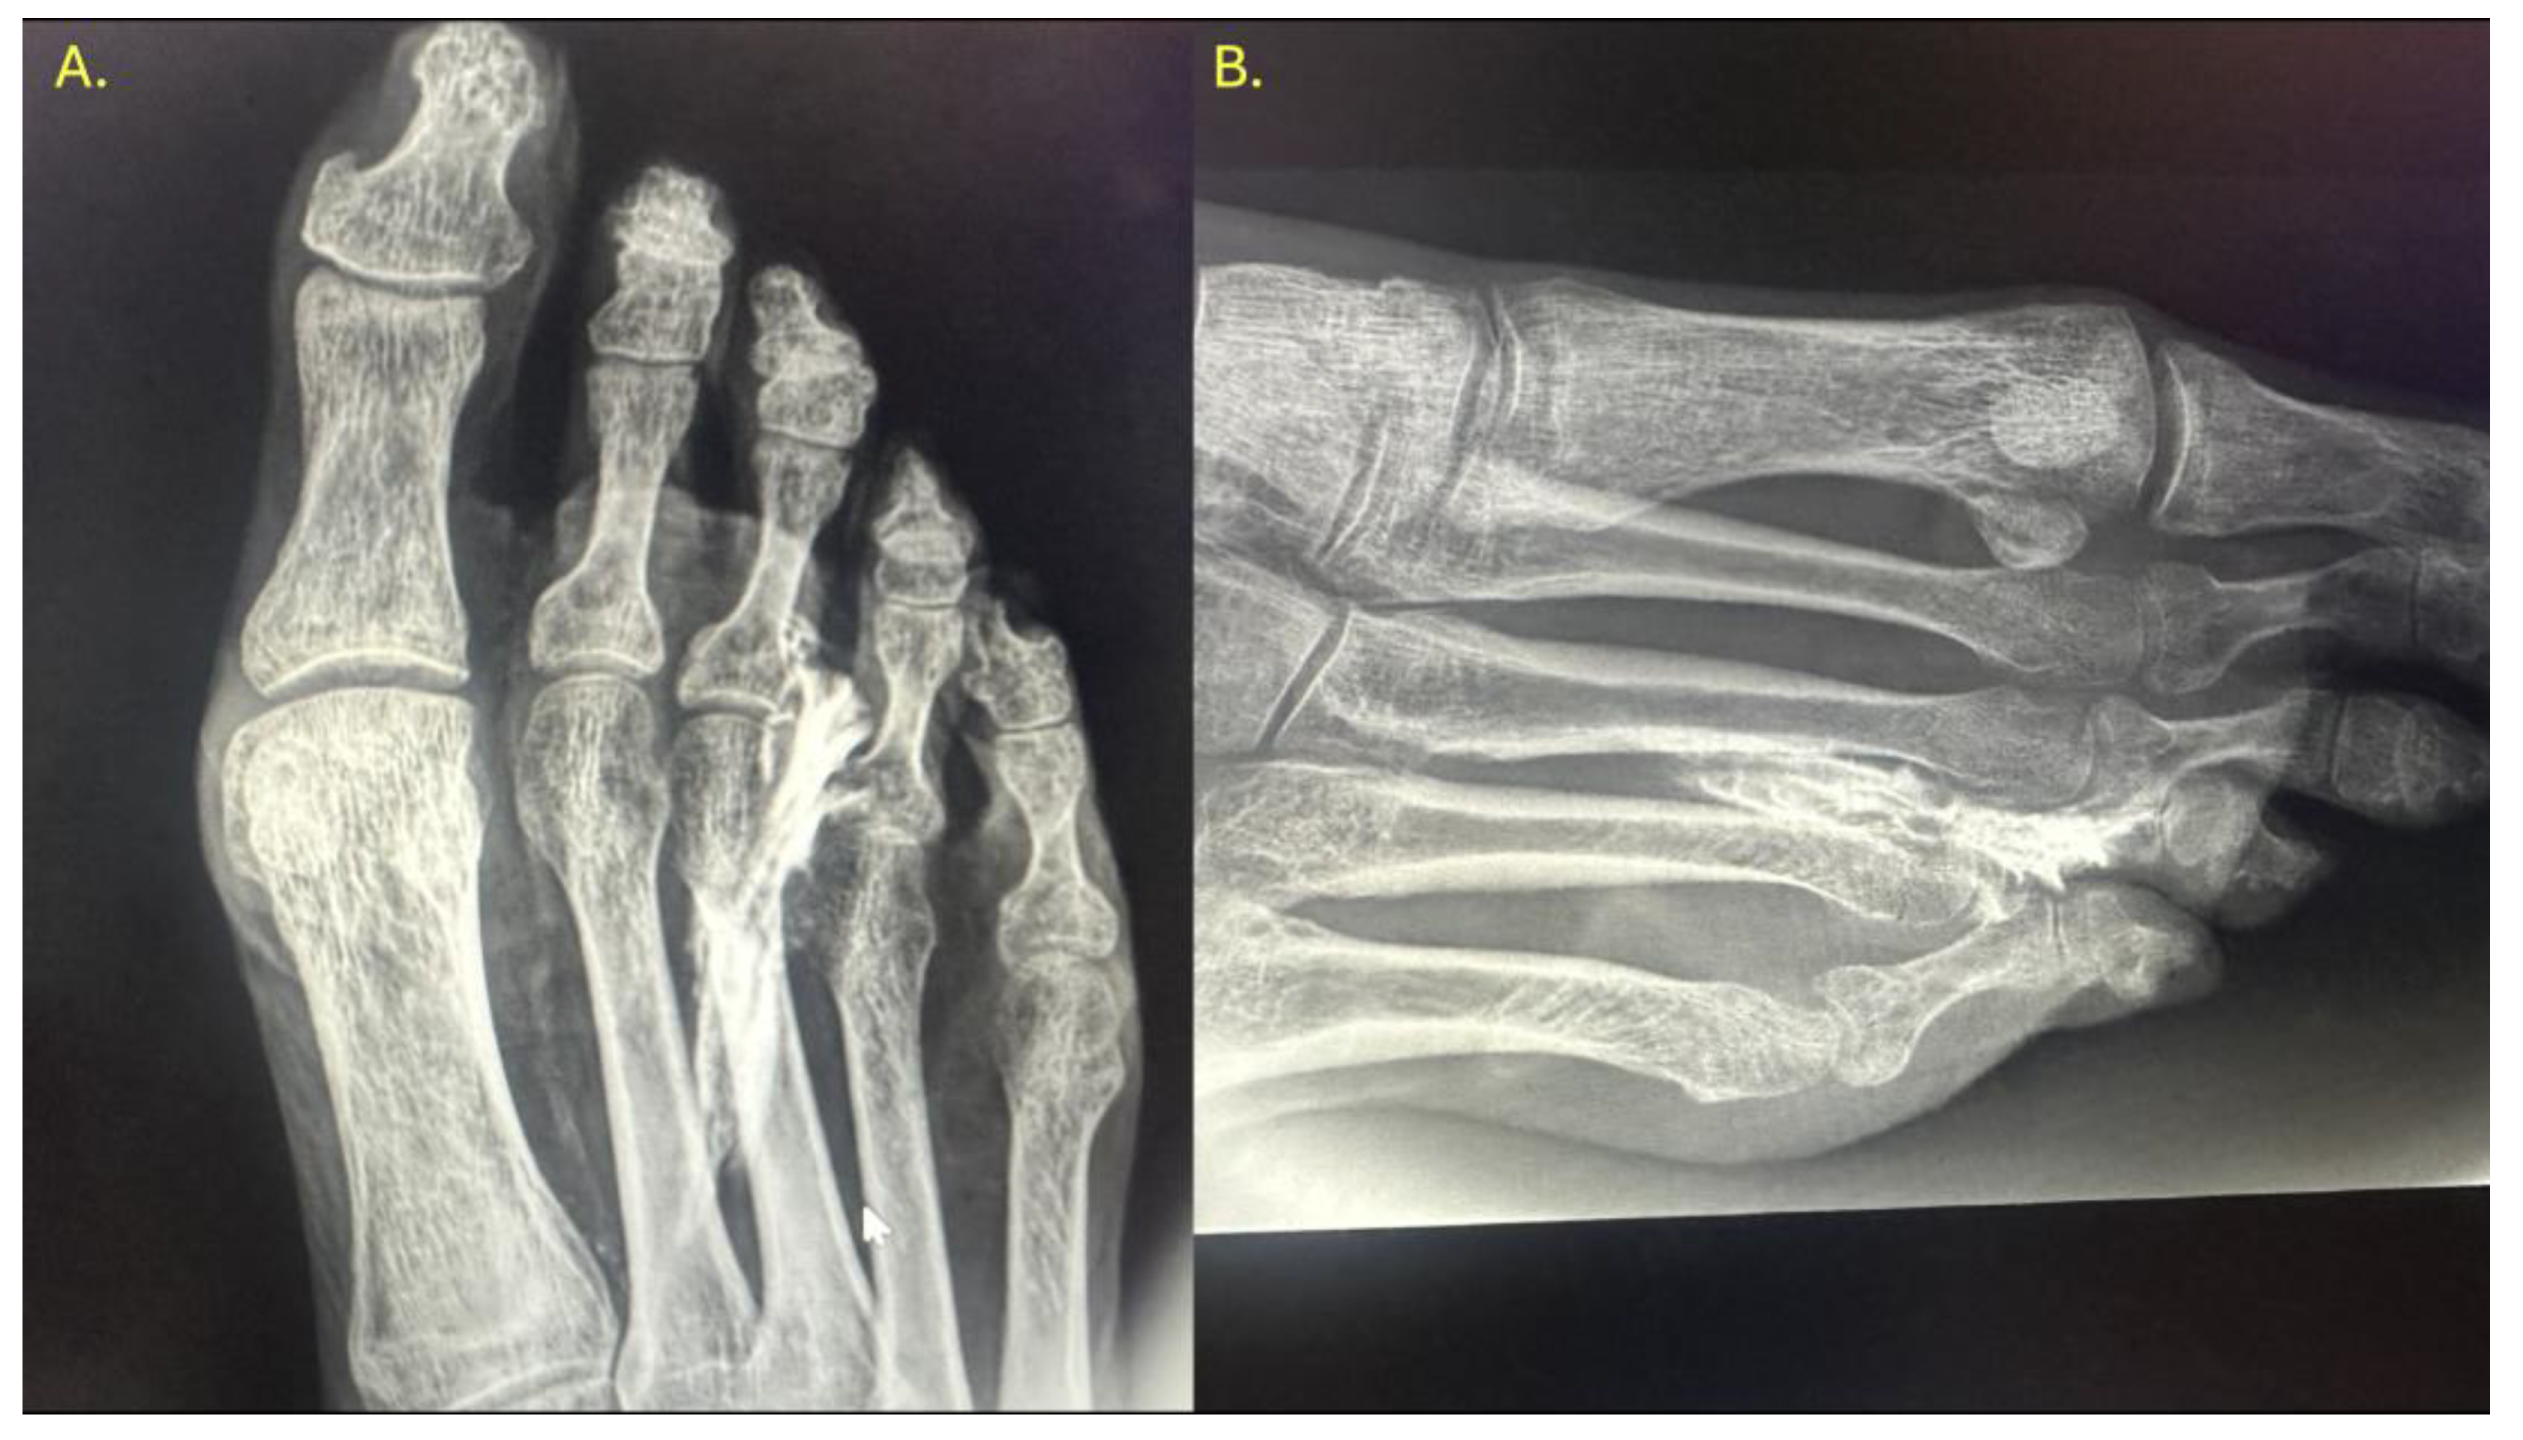

The procedure was performed using high-resolution ultrasound (10–15 MHz linear transducer) under real-time guidance (Figure 1), following the selective infiltration protocol described by Ruiz Santiago et al. for Morton’s neuroma (3). Three injections were performed on each anatomical specimen: 1- Metatarsophalangeal joint of the third ray (3rd MTP joint), 2- Metatarsophalangeal joint of the fourth ray (4th MTP joint) and 3- Intermetatarsal space between the third and fourth rays (IM space).

Figure 1. Longitudinal (long-axis) ultrasound image of the ultrasound-guided injection into the second metatarsophalangeal joint.